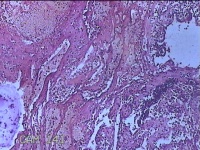

性别

女

年龄

41岁

临床诊断

异常子宫出血(无排卵型子宫出血) 子宫肌瘤

一般病史

阴道流血12天。

标本名称

宫腔内容物

大体所见

灰白暗红色不规则碎组织2.5x2x0.8cm一堆。

图1